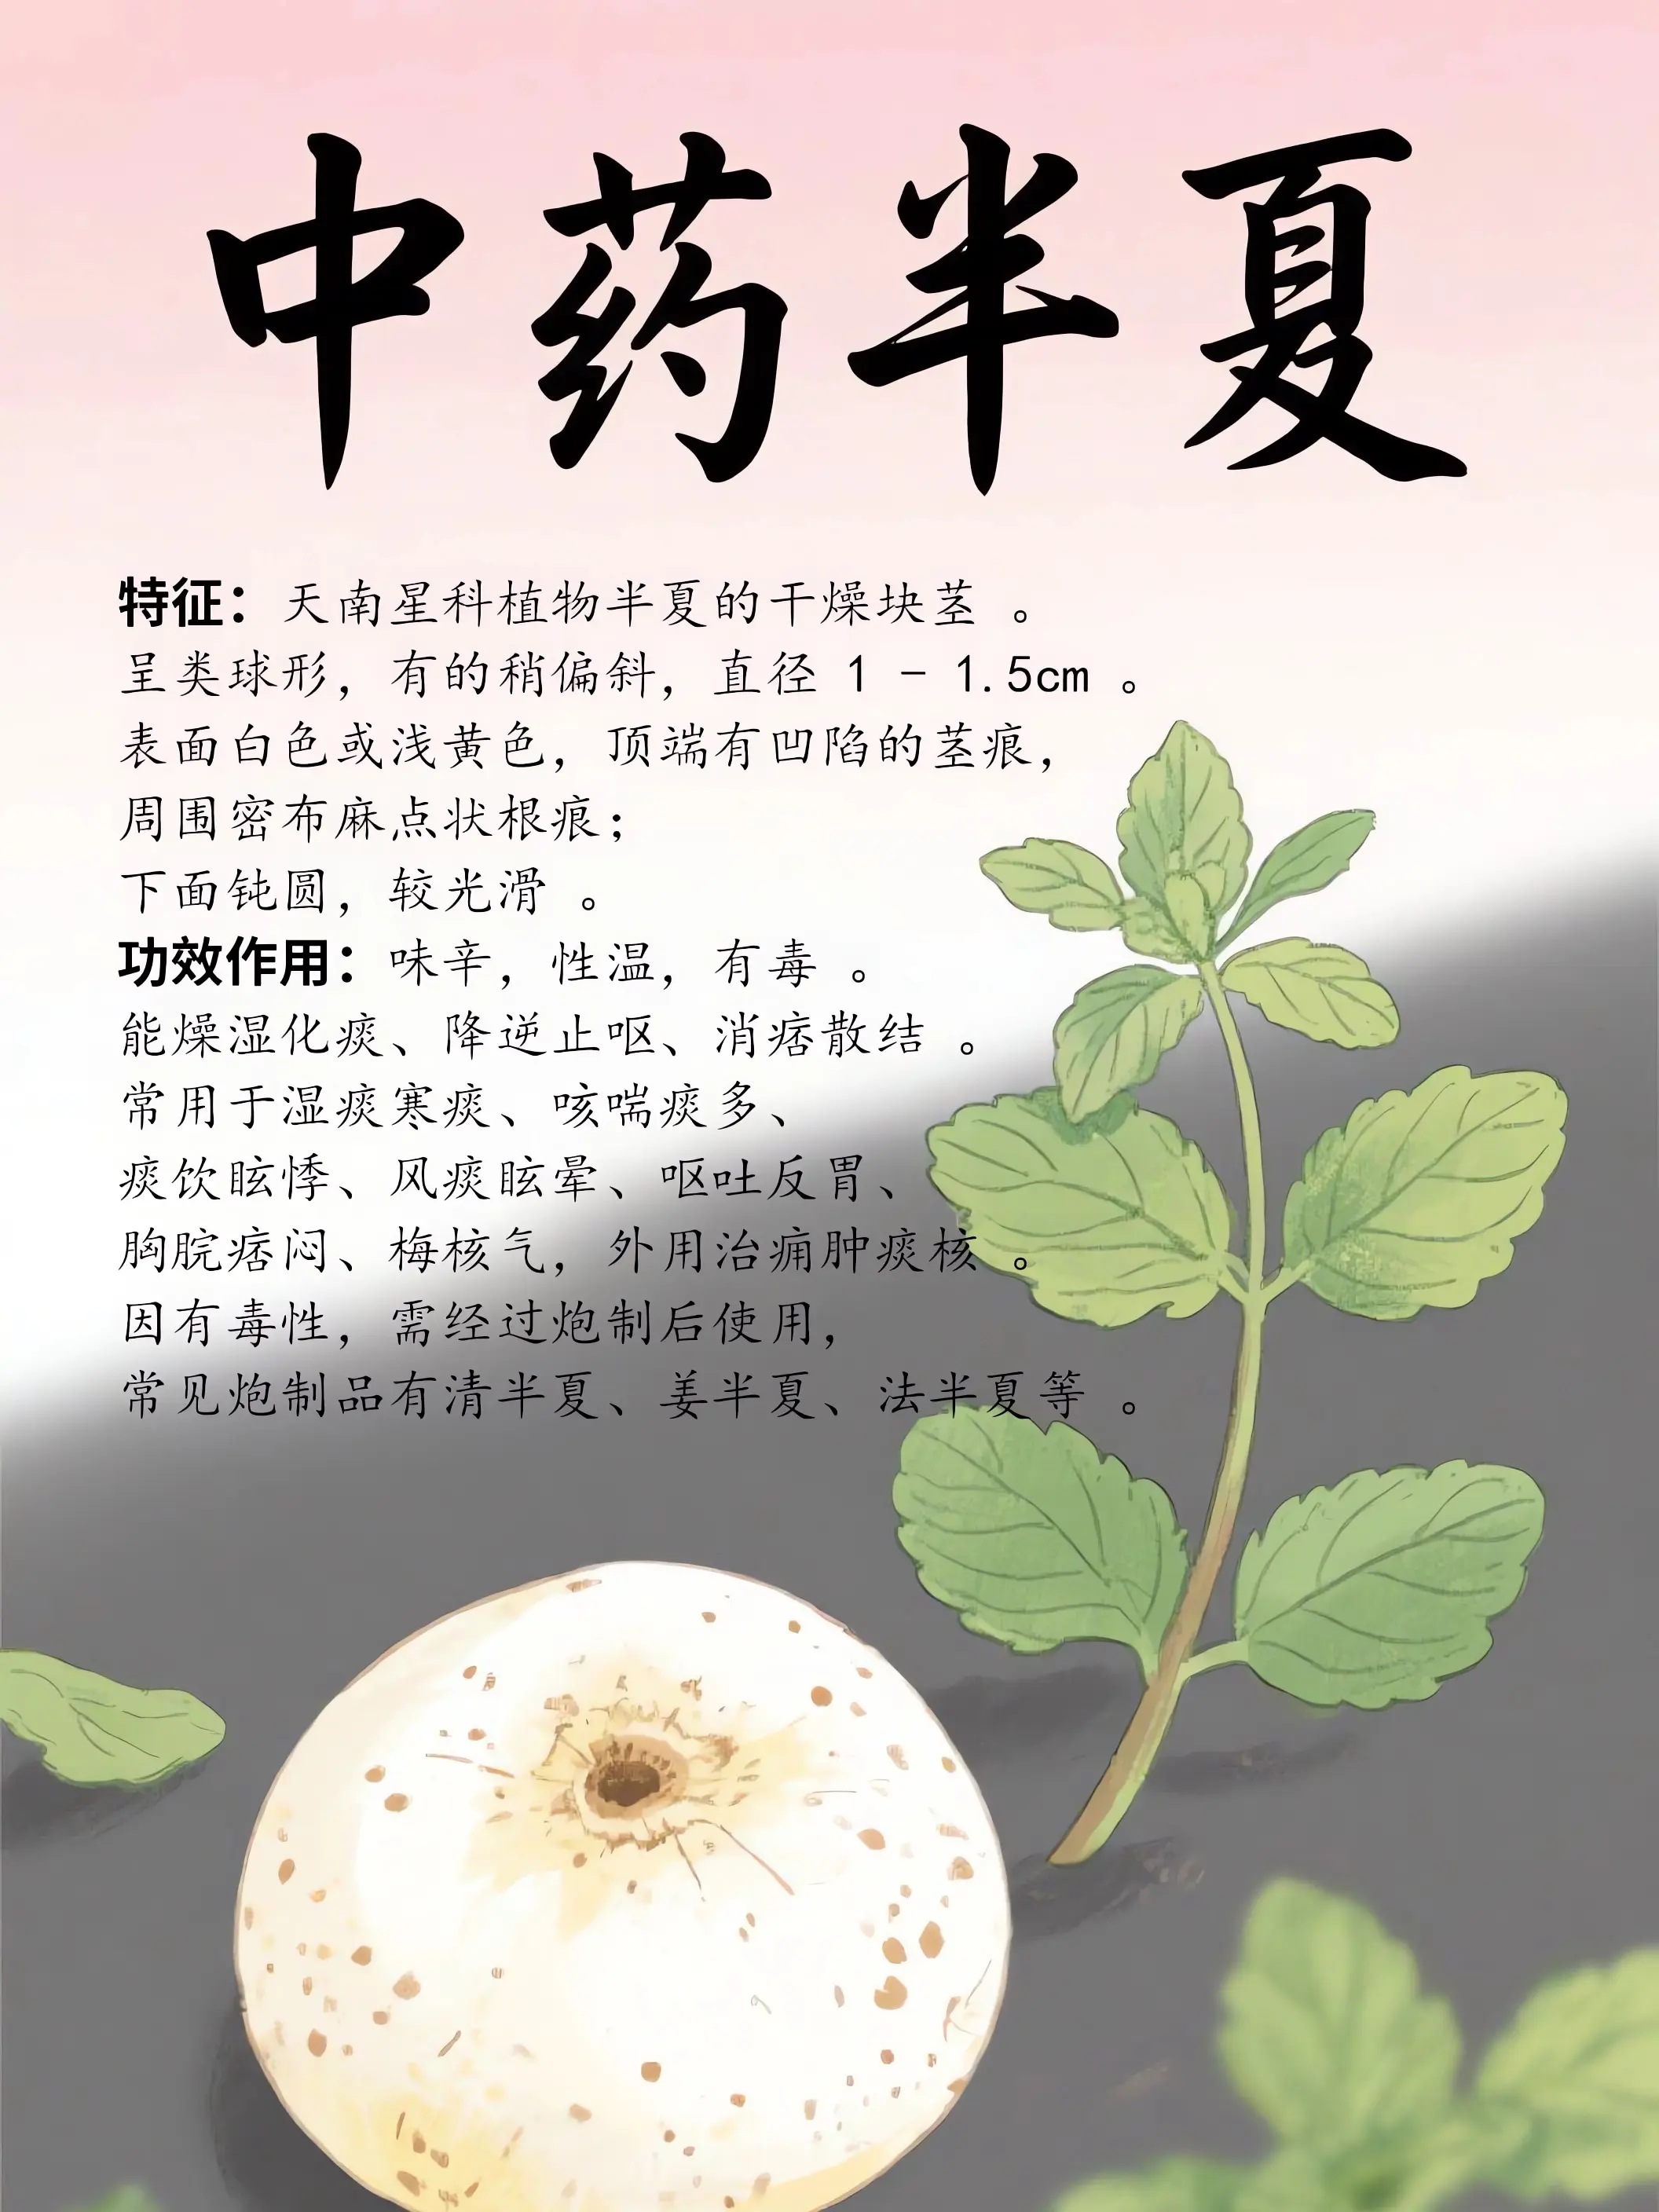

中藥知識科普...

211人浏覽中